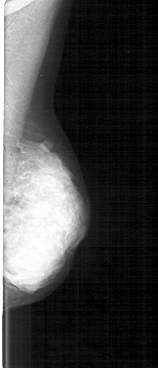

D_4118_1.RIGHT_MLO

FILE: D_4118_1.RIGHT_MLO.OVERLAY

TOTAL_ABNORMALITIES 1

ABNORMALITY 1

LESION_TYPE CALCIFICATION TYPE PLEOMORPHIC DISTRIBUTION SEGMENTAL

ASSESSMENT 5

SUBTLETY 5

PATHOLOGY MALIGNANT